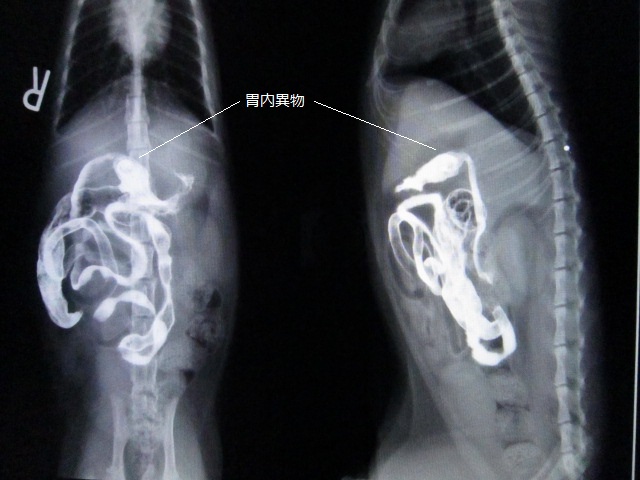

次の日のレントゲンです。

バリウムは結腸まで通貨していますが、胃内に不透過物が残っています。